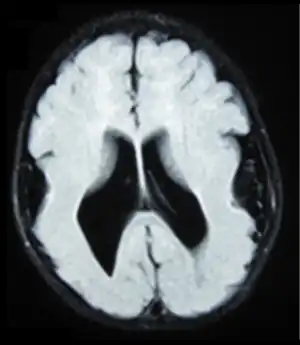

| Lissencephalic brain of a human, lacking surface convolutions (Gyrification) | |

Lissencephaly (meaning "smooth brain")[1] is a set of rare brain disorders where the whole or parts of the surface of the brain appear smooth.[2] It is caused by defective neuronal migration during the 12th to 24th weeks of gestation resulting in a lack of development of brain folds (gyri) and grooves (sulci).[3] It is a form of cephalic disorder. Terms such as agyria (no gyri) and pachygyria (broad gyri) are used to describe the appearance of the surface of the brain.

Symptoms of lissencephaly are detected via ultrasound at about twenty-three weeks and require confirmation from a prenatal MRI. It is characterised by absence or reduction of the sulci and gyri of the cerebral surface and a thickened cortex.[5]

There are anatomical symptoms that differ across the two main types of lissencephaly, Classical (Type I) and Cobble Stone (Type 2). In Classical lissencephaly the cortex becomes thickened and can be identified by four layers of the cerebral cortex rather than six.[5]